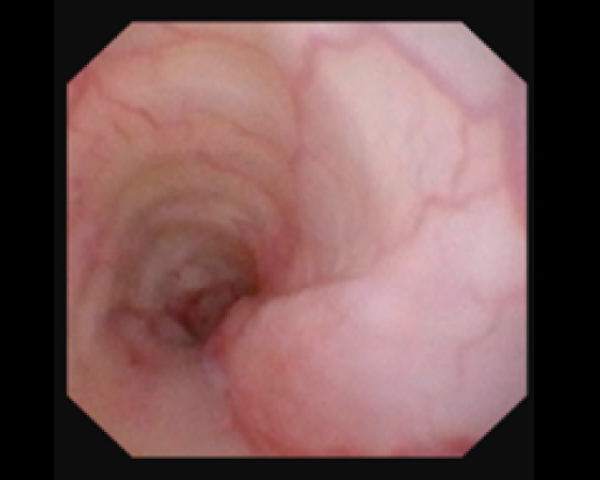

内視鏡で狭窄部位を確認